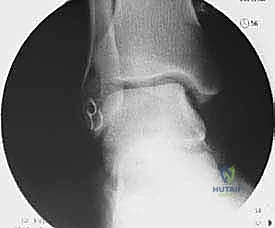

التشريح الدقيق للكاحل: فهم بنية الأربطة الجانبية

لفهم طبيعة الإجراء الجراحي، يجب أولاً فهم التشريح المعقد للكاحل. يتكون مفصل الكاحل من التقاء ثلاثة عظام: الظنبوب (القصبة)، الشظية، وعظم الكاحل (Talus). لضمان ثبات هذا المفصل أثناء الحركة، يتم دعمه بشبكة قوية من الأربطة.

الأربطة الجانبية (الموجودة في الجزء الخارجي من الكاحل) هي الأكثر عرضة للإصابة، وتتكون من ثلاثة أربطة رئيسية:

- الرباط الكاحلي الشظوي الأمامي (ATFL): هو أضعف الأربطة الجانبية والأكثر تمزقاً أثناء التواء الكاحل للداخل (Inversion).

- الرباط العقبي الشظوي (CFL): رباط قوي يساعد في استقرار الكاحل والمفصل تحت الكاحل. يتمزق عادة في الإصابات الأكثر شدة.

- الرباط الكاحلي الشظوي الخلفي (PTFL): هو الأقوى ونادراً ما يتمزق إلا في حالات الخلع الكامل للكاحل.

عندما تتمزق هذه الأربطة ولا تلتئم بشكل صحيح، تصبح رخوة وضعيفة. هذا التراخي يؤدي إلى حركة غير طبيعية لعظم الكاحل داخل المفصل، مما يسبب احتكاكاً مفرطاً وتآكلاً لغضروف المفصل بمرور الوقت.